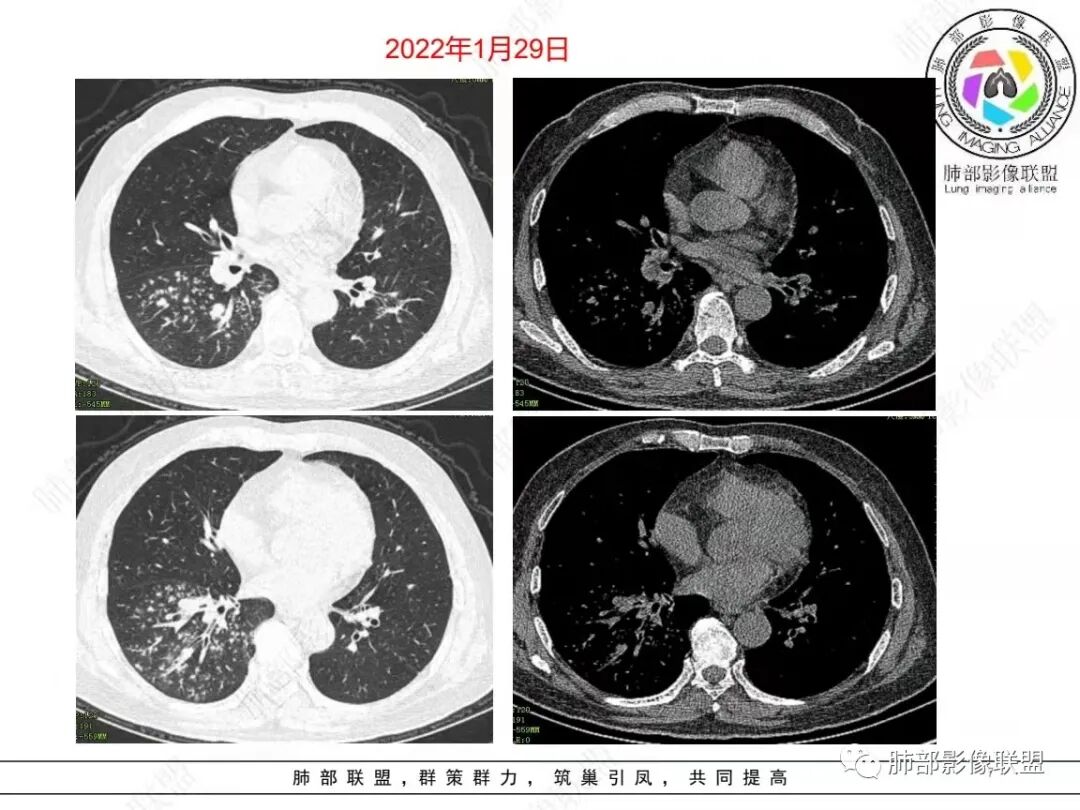

老年男性,糖尿病人,右下肺弥漫性小叶核心结节,治疗10天后明显吸收,血象高,中性粒细胞计数高,pct略高,首先考虑金葡菌感染,鉴别G-肠杆菌

右肺下叶多发腺泡结节影,边缘部分模糊,伴树芽征,支气管壁增厚,10天复查腺泡结节有吸收变淡,病变内出现多发囊状影,考虑感染性病变,金葡?真菌?

右肺下叶多发腺泡结节影及树芽征,抗炎治疗后吸收好转,白细胞及中性明显增高,有糖尿病病史,首先考虑气道来源感染性病变,金葡菌?吸入?

中年男性,咳嗽咳黄脓痰一周,有糖尿病,肾病病史,长期使用激素血象白细胞自然会升高,但CRP明显升高。降钙素原不高,肺泡灌洗液阴性。右下肺沿支气管分布腺泡结节影,少于树芽征,小实变影,支气管壁轻度增厚,考虑感染性疾病,从病灶形态来看气道来源,复查病灶有小空洞形成,病灶明显吸收。考虑气道金葡菌肺炎,鉴别奴卡菌

中老年 男性 白细胞高,基础病多, 右肺下叶多发小结节 小斑片影,边缘模糊,伴树芽征,支气管壁略增厚,短期治疗后复查病灶有所吸收,可见小囊状透光区形成,考虑气道来源化脓性感染,金葡 可能

中老年男性,糖尿病史,免疫抑制,白细胞及C反应蛋白明显升高,右肺下叶多发腺泡结节、树芽,边缘模糊,支气管管壁增厚,治疗10日复查吸收好转,可见小空洞,考虑金葡,鉴别曲霉

病变区支气管壁弥漫增厚,远端树芽征,周围GGO——渗出